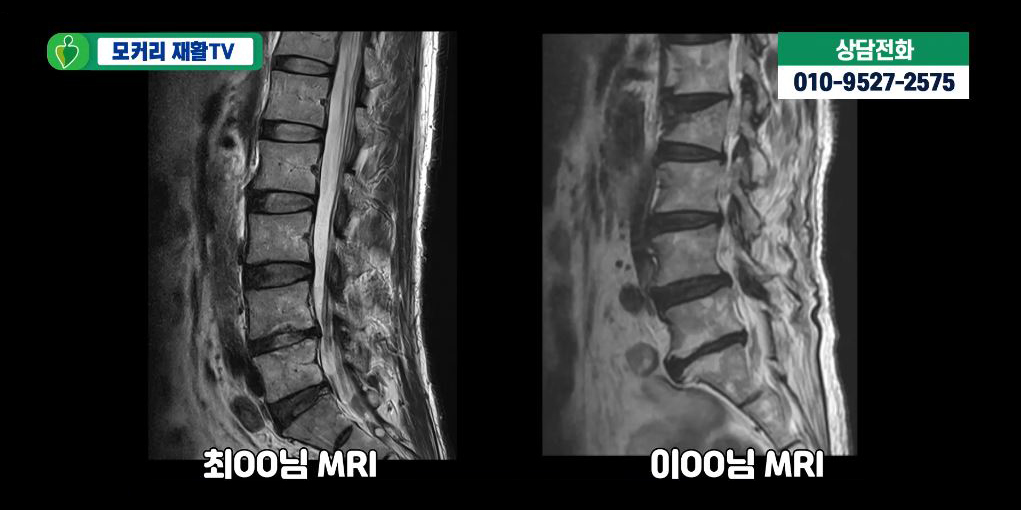

아래 사진은 실제 근감소증 환자들의 MRI입니다.

이 환자분들의 MRI를 보면 두분 다 60세 이상이시라 노화로 인해 MRI상으로 협착과 퇴행성디스크가 보입니다.

하지만 협착이 심하지 않아서 다리로 가는 신경을 누르는 것 같지는 않습니다. 이분들의 엉덩이나 다리증상이 협착증 증상이 아닐 가능성이 높은 것입니다. 그럼에도 불구하고 이분들처럼 MRI로 퇴행성디스크와 협착이 보이고 허리와 다리가 아프면 무조건 협착증이라고 진단하는 경우가 매우 많습니다. 이분들도 역시 협착과 퇴행성디스크 진단을 받았습니다. 하지만 이분들의 허리통증, 엉덩이통증, 다리증상과 걷는 게 힘든 증상은 협착과 퇴행성디스크 문제보다는 근감소증과 근육 뭉침 때문입니다.

보시다시피 두분 다 척추기립근도 지방화가 심하게 돼있고, 근감소증 검사에서도 양성반응을 보이셨습니다. 이렇듯 협착증이 아닌데 협착증으로 잘못 진단하게 되면 엉뚱한 치료를 받으면서 시간만 낭비하고, 또 고생은 고생대로 하면서 치료가 안 되는 그런 결과를 낳게 됩니다. 따라서 반드시 협착증과 근감소증을 잘 구별해야 하며, 최근에 유달리 근육이 많이 줄어들었고, 특히 허리가 아프고 구부러지며, 걸음걸이가 느려지면서 다리가 아픈 증상이 나타난다면 근감소증 검사를 받아볼 필요가 있습니다.